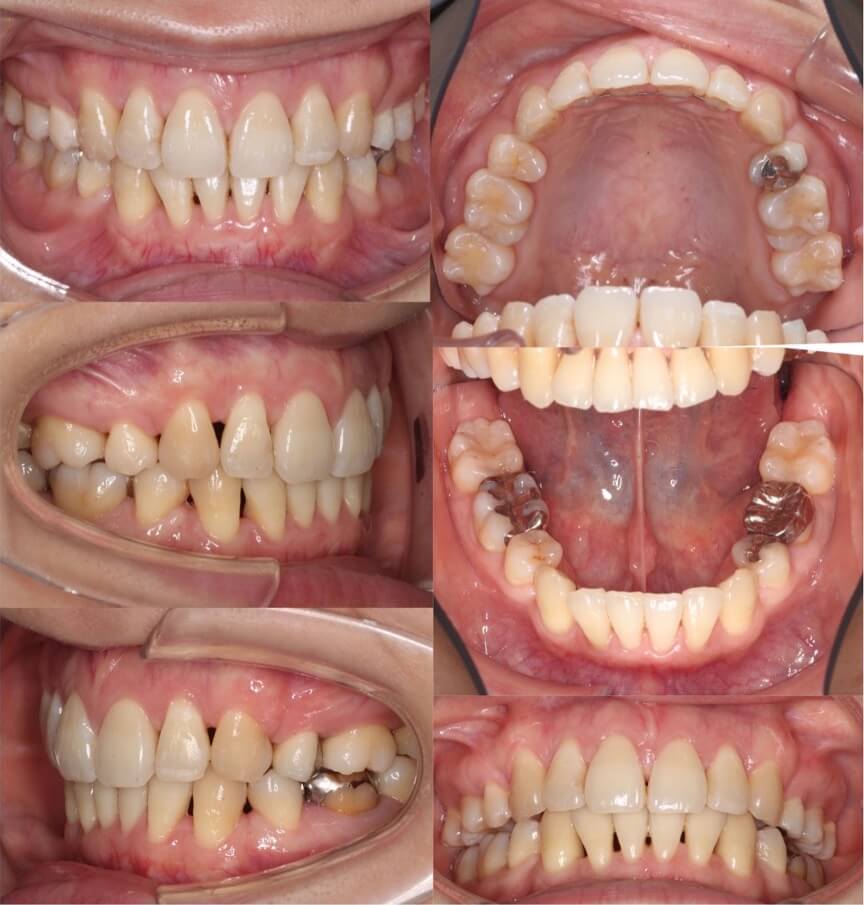

「顔のサイズが小さくなる」

大学生女性・ハーフリンガル装置・前歯傾斜型装置・下あご後退型

歯並びの見た目はあまり悪くはないのですが、口元のの突出の改善を希望されていました患者さんです。上下顎抜歯を併用して矯正治療を行いました。ゆっくりとお顔が変化するのを楽しんで治療を受けてくれていました

<症例概要>

主訴:出っ歯を治したい

年齢・性別:大学生女性

住まい:千葉県八千代市

症状:下顎後退・上下顎前歯唇側傾斜

治療方針:抜歯空隙の閉鎖(最大固定)

治療装置:ハーフリンガル矯正装置(上のみ裏側装置)

固定:歯科矯正用アンカースクリュー(口蓋側壁x2)

抜歯:上下第一小臼歯

治療期間:2年1か月

リテーナー:上プレートタイプ+クリアタイプ・下フィックスタイプ

治療費用:1,495,000(税込)

代表的副作用:痛み・治療後の後戻り・歯根吸収・歯髄壊死・歯肉退縮

▶︎その他の副作用